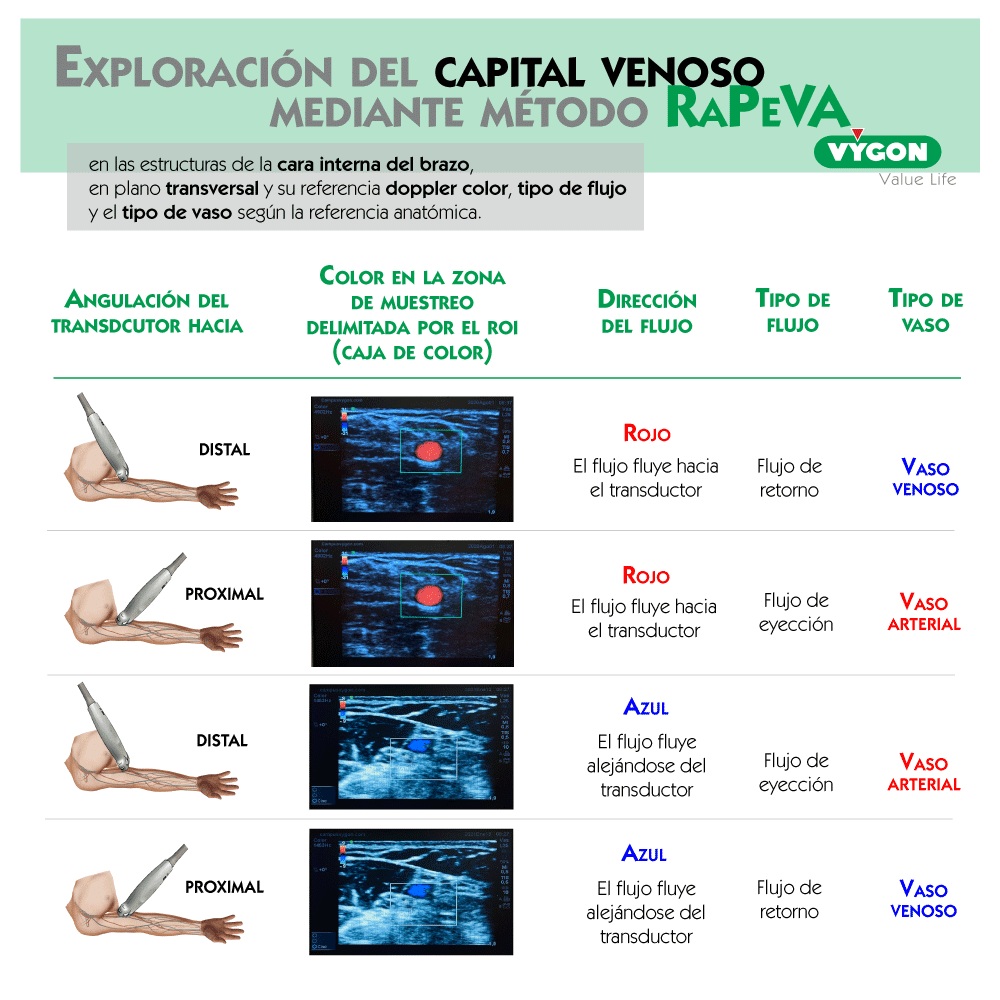

Tras iniciar la exploración del capital venoso, mediante el método RaPeVA (desarrollado por el grupo GAVeCeLT), podemos aplicar el doppler color para identificar y diferenciar las estructuras arteriales y venosas.

Manteniendo la exploración en modo B, activamos el modo doppler color y situamos el ROI o cuadro de color en la estructura que queramos estudiar, asignando un tamaño adecuado al mismo.

Posteriormente, angulamos el transductor entre 30 a 60º o bien hacia la parte distal del cuerpo (hacia la mano), o hacia la parte proximal (hacia la cabeza). Por último, volvemos a activar el modo doppler color para que comience el análisis, obteniendo una tonalidad roja al identificar el flujo que fluye hacia el transductor o azul si éste, se aleja.

En el estudio de las extremidades, si basculamos la sonda de tal manera que los ultrasonidos se dirigen hacia la cabeza del paciente, los vasos que veamos en color rojo serán arterias y los que veamos en color azul serán venas. En la tabla adjunta se muestran las diferentes combinaciones con las que estudiar el capital vascular del paciente con modo doppler color en plano transversal.